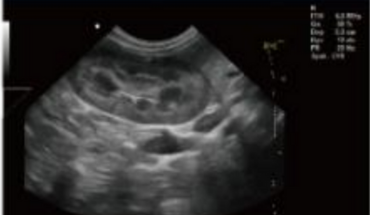

- Equipped with a Wide Range of Probes for Abdominal, Obstetric, Vascular, Cardiac, Small Organ, Urinary Applications

- 3.5 MHz Convex Wide-band Probe

- 6.5MHz Micro Convex Probe